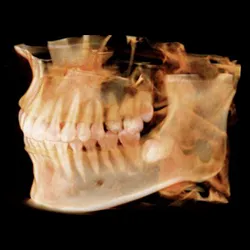

Case 4